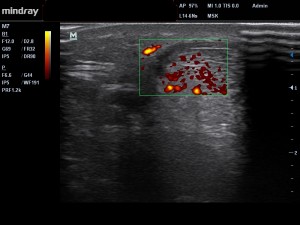

Fig3. Le doppler puissance retrouve une inflammation active (points jaunes/rouges

Chez notre patient, l’échographie (Fig 1 – 3 ) montre la présence d’un mécanisme inflammatoire actif, avec présence d’un exsudat au niveau de para-tendon.  On parle précisément d’inflammation fibrineuse dans notre cas. SI la pathologie s’installe dans le temps, la présence de fibrinogène (grosse protéine présente dans le plasma sanguin) va conduire à la prolifération de fibroblastes (petites cellules notamment impliquées dans la fabrication du collagène et certaines protéines du tissu conjonctif ). Le para-tendon va alors s’épaissir, et des adhérences vont se former entre le para-tendon et le tendon, mettant en péril la vascularisation de ce dernier.